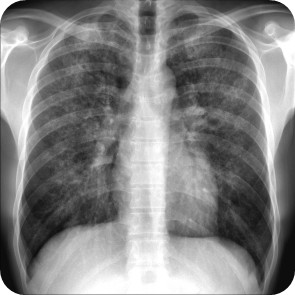

5 / 5

5. A 32-year-old renal transplant recipient presents with low-grade fever, dry cough, and dyspnea. Chest X-ray (shown in the image) demonstrates diffuse perihilar hazy opacities. His immunosuppressive regimen includes cyclosporine, prednisolone, and mycophenolate mofetil. HIV screening was later found positive. Sputum cultures, AFB, Gram stain, and CMV PCR are negative. What is the most likely diagnosis?